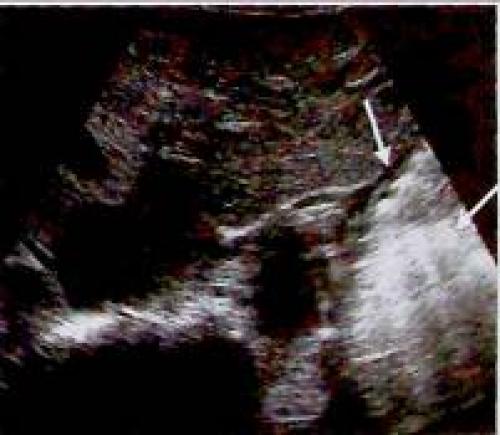

Дополнительные возможности визуализации слоёв стенки желудка предоставляет эндосонография

Рис. 2. Эндосонография желудка

Эндосонографическое представление слоев стенки желудочно-кишечного тракта: Просвет желудка (26) Эхогенная поверхность слизистой (а) Низкой эхогенности слизистая (b) Эхогенная подслизистая (с) Низкой эхогенности мышечный слой (d) Эхогенная серозная оболочка (е)

Эндосонография является необходимым и высокорезультативным методом диагностики при подслизистых опухолях желудка и при определении стадии его злокачественных новообразований.